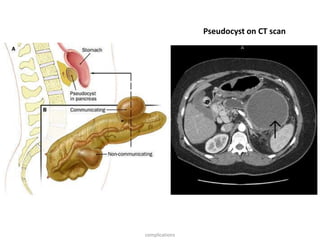

Pseudocyst Encapsulated fluid collection with high enzyme

content. Usually less than 6cm sized pseudocysts

resolve spontaneously. They may become secondarily

infected requiring drainage of abscess.

Pseudocyst on CT scan

Complications of acutepancreatitis Pancreatic complications Causes and features Necrosis Abscess Rising fever, leukocytosis, localized tenderness and epigastric mass. It may be associated with left sided pleural effusion and enlarged spleen due to splenic vein thrombosis. Pseudocyst Encapsulated fluid collection with high enzyme content. Usually less than 6cm sized pseudocysts resolve spontaneously. They may become secondarily infected requiring drainage of abscess. Ascites Gradual increase in abdominal girth and persistent elevation of serum amylase in the absence of frank abdominal pain. It results from rupture of pancreatic duct or drainage of pseudocyst into the pancreatic cavity. complications